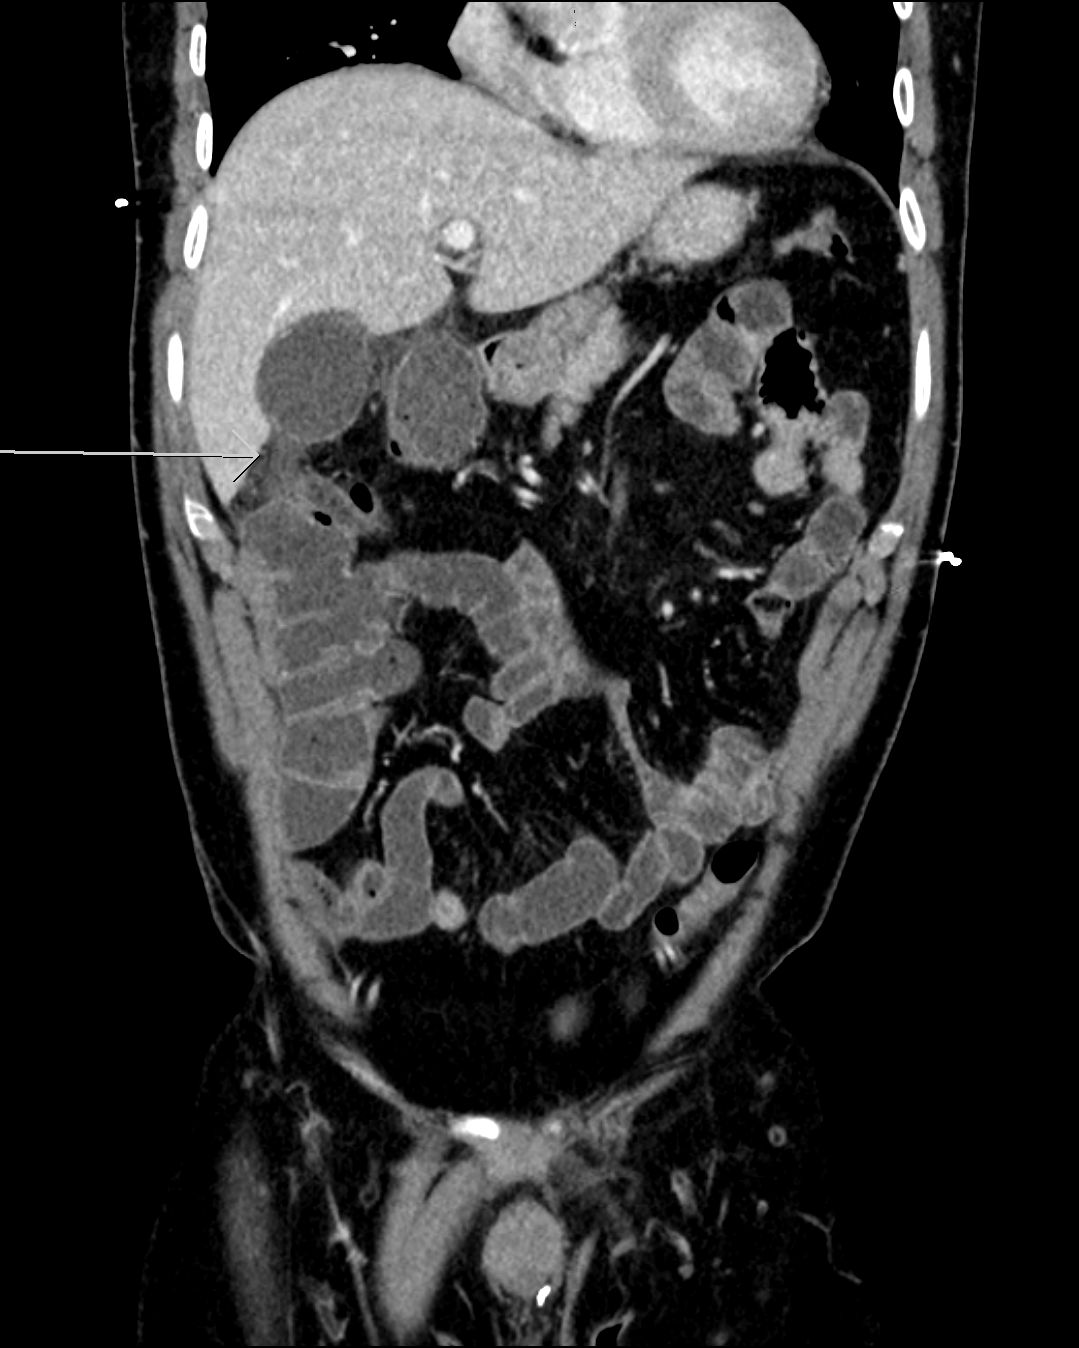

The patient was referred to ultrasound with suspicion of acute cholecystitis as a possible primary diagnosis and acute appendicitis as a secondary possibility. An ultrasound examination of the abdomen was performed using a GE Logiq E9 system with a curved array transducer with a frequency of 1-6 MHz (GE, Chalfont St. Giles). The examination revealed sludge and a stone of approximately 1 cm in the gallbladder. There was no dilatation of the intra- or extrahepatic bile ducts and the gallbladder wall was without thickening (below 3 mm). The other abdominal organs were normal. The appendix could not be seen. Due to the discrepancy between the clinical history, the imaging findings and the planned cardiac surgery the day after, a CT examination was performed to exclude appendicitis. CT showed pericholecystic fat stranding, confirming the diagnosis of cholecystitis. The appendix was located behind the cecum and appeared normal. No other pathology was reported.